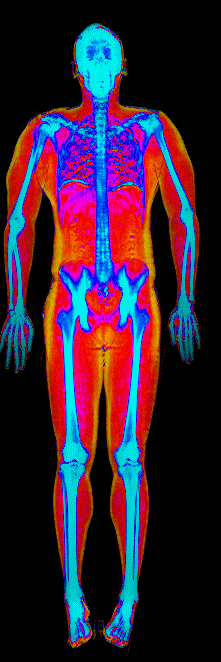

What Fat Loss Looks Like on a DEXA Scan

Red = muscle, gold = fat, blue = bone.

Lost 26.0 lb of fat · 187 → 150 lb · Age 44

Lost 25.4 lb of fat, gained 3.7 lb lean · 201 → 180 lb · Age 33

Lost 24.9 lb of fat, gained 12.0 lb lean · 183 → 170 lb · Age 37